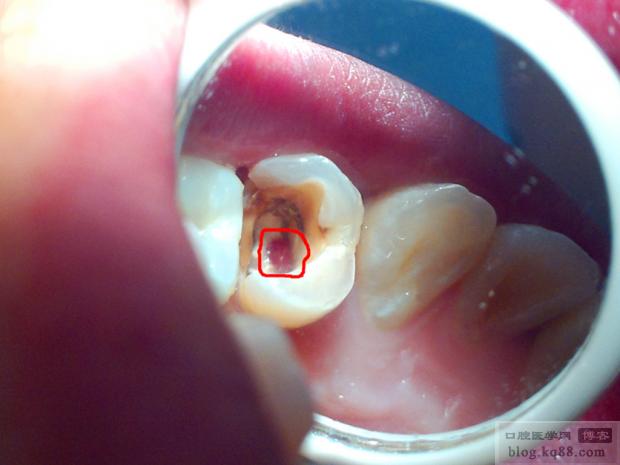

- 立即发现: 在操作中(尤其是使用显微镜时)或术后X光片发现侧穿。

- 精确放置: 在显微镜下操作,确保材料仅覆盖穿孔区域,避免进入根管或牙周间隙,使用专用输送器(如MTA输送器、Biodentine注射器)。

(图片来源网络,侵删)完成根管充填后,按照常规进行牙体修复(桩核+全冠),恢复牙齿外形和功能,防止牙折。